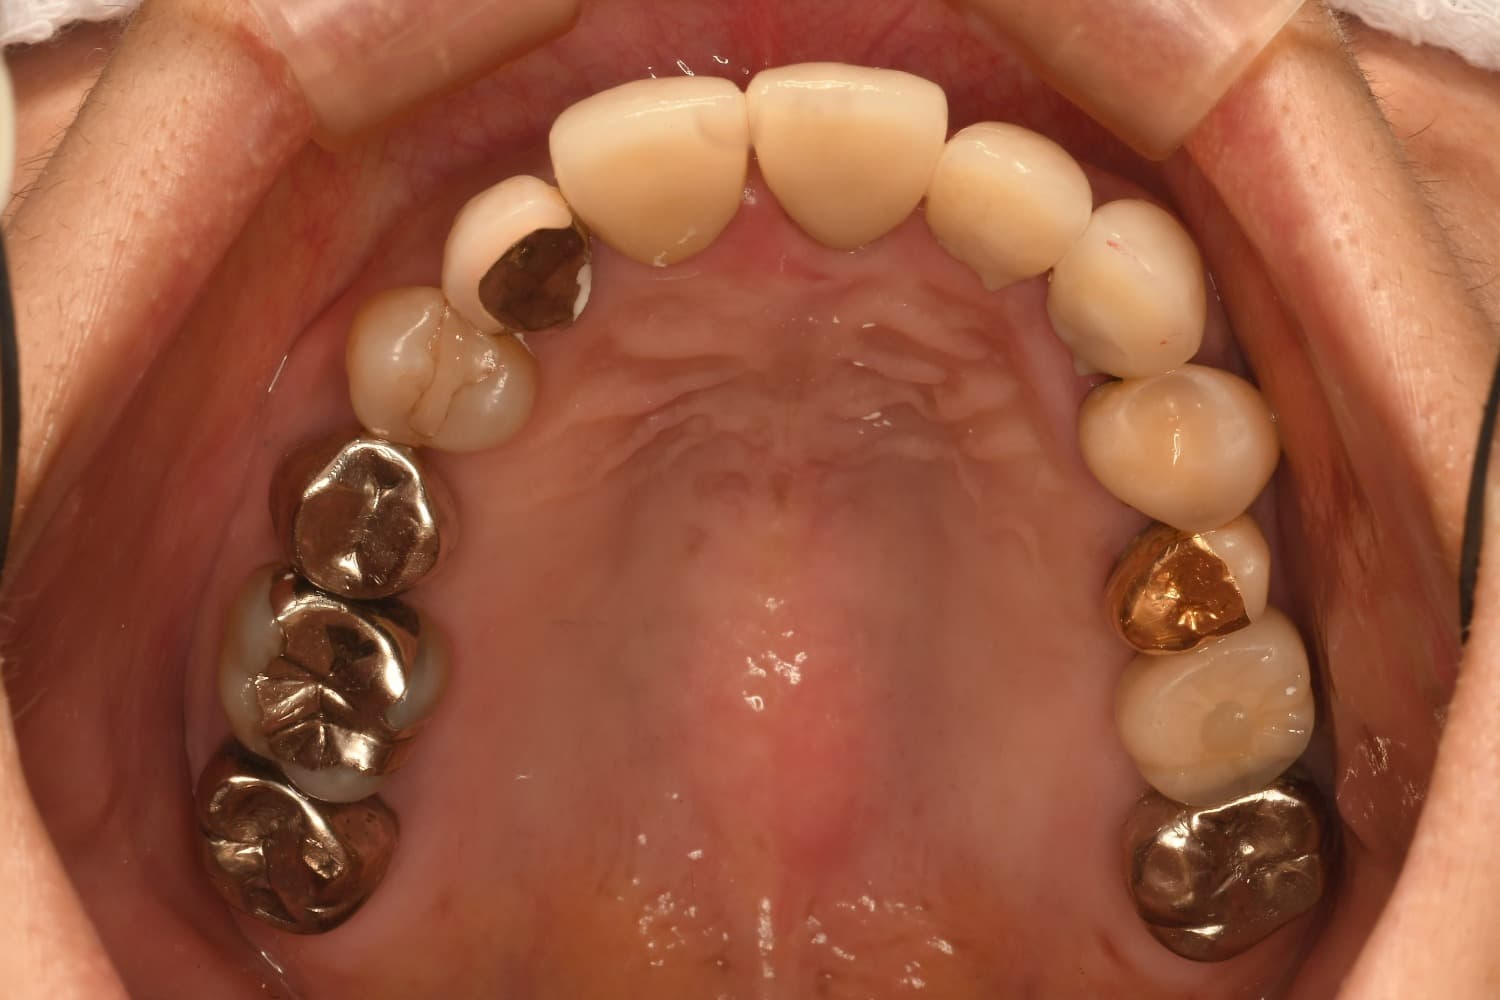

After

左上6番の抜歯と同時に骨を増やす処置(GBR)を行い、2カ月後の精密検査で土台の回復を確認します。インプラントプレミアムコースで、安全にインプラントを埋入します。